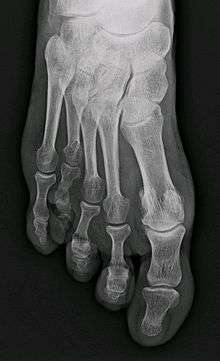

Brachymetatarsia or hypoplastic metatarsal is a condition in which there is one or more abnormally short or overlapping toes metatarsals.[1] This condition may result due to a congenital defect or it may be an acquired condition.[1] It most frequently involves the fourth metatarsal. If it involves the first metatarsal, the condition is known as Morton's syndrome.[1] Treatment is via a number of differing surgical procedures.[1]

Brachymetatarsia is found to occur more frequently in women than men.[1]